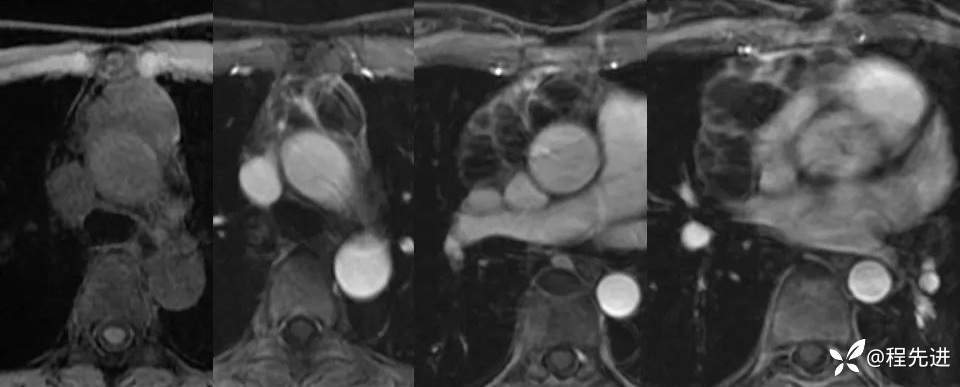

增强